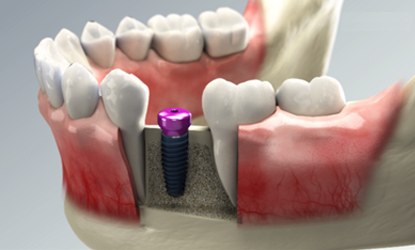

Step 03

Abutment placement

The abutment is the connecting element between the crown and the implant.

The abutment is connected to the implant during or after the healing period, depending on the stability of the implant that gradually integrates with the surrounding bone to create a strong and lasting foundation.